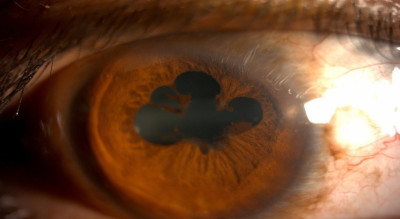

मोतीबिंदू (Cataract)

मोतीबिंदू म्हणजे डोळयाच्या बाहुलीतले भिंग नेहमीप्रमाणे काचेसारखे पारदर्शक न राहता तांदळाच्या दाण्यासारखे पांढुरके होते. यामुळे प्रकाशकिरण आत शिरायला अडथळा होतो. मोतीबिंदू सहसा उतारवयात येतो. मधुमेहात तो लवकर येऊ शकतो.

मोतिबिंदूची लक्षणं

मोतीबिंदू आल्यावर नेहमीची तक्रार म्हणजे अंधुक दिसणे. रात्री गाडी चालवतांना समोरचा लाईट जास्त त्रासदायक होतो. दिव्याभोवती रंगीत कडी दिसतात. डोळयांसमोर काळे वर्तुळ दिसते. दिवसा (जास्त प्रकाशात) कमी दिसते. पण संध्याकाळी (कमी प्रकाश असतो तेव्हा) दिसण्यात थोडी सुधारणा होते, एकाऐवजी अनेक प्रतिमा दिसणे हे पण एक लक्षण आहे. कालपरत्वे दूरच्या आणि जवळच्याही वस्तू दिसणं बंद होतं. म्हणजेच मोतिबिंदू पिकतो. जास्त पिकल्यास काचबिंदूही होऊ शकतो. मोतीबिंदू किती पिकला आहे यावर तक्रारींचे स्वरूप अवलंबून असते इत्यादी.

मोतीबिंदू लवकरात लवकर शस्त्रक्रिया करून काढून त्याऐवजी डोळयातच कायमचे भिंग बसवले जाते. मात्र औषधाने मोतीबिंदू घालवणे शक्य नाही. तसेच उन्हामुळे मोतीबिंदू जास्त प्रमाणात व लवकर होतो. उन्हात काम करताना गॉगल लावणे चांगले. डोळयावर सावली येईल अशी टोपी वापरणे हा पण चांगला प्रतिबंधक उपाय आहे.

प्रमुख कारणं

• वाढत्या वयानुसार नैसर्गिक भिंगातील प्रथिनांमध्ये बदल होऊन ते अपारदर्शक होतात.

• डोळ्यांना इजा झाल्यास.

• डोळ्यांच्या इतर आजारांमुळे.

• स्टेरॉइडसारखी औषधं दीर्घकाळ वापरल्यामुळे.

• मधुमेह असणाऱ्या रुग्णांमध्ये मोतिबिंदू लवकर होतो.

• काही रुग्णांना जन्मतः मोतिबिंदू असतो.

मोतीबिंदू शस्त्रक्रिया (Cataract Surgery)

मोतिबिंदू कोणत्याही औषधाने अथवा चष्मा वापरून कमी होत नाही. शस्त्रक्रिया हाच एकमेव कायमस्वरूपी उपचार आहे. यात अपारदर्शक भिंग काढून कृत्रिम भिंगारोपण केलं जातं.